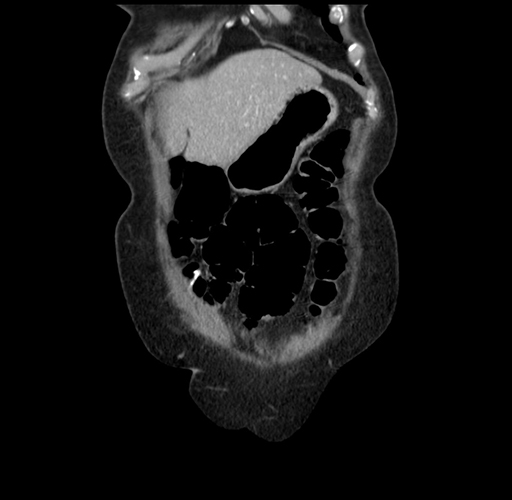

Pre-Chemo: Coronal Venous

Coronal Venous